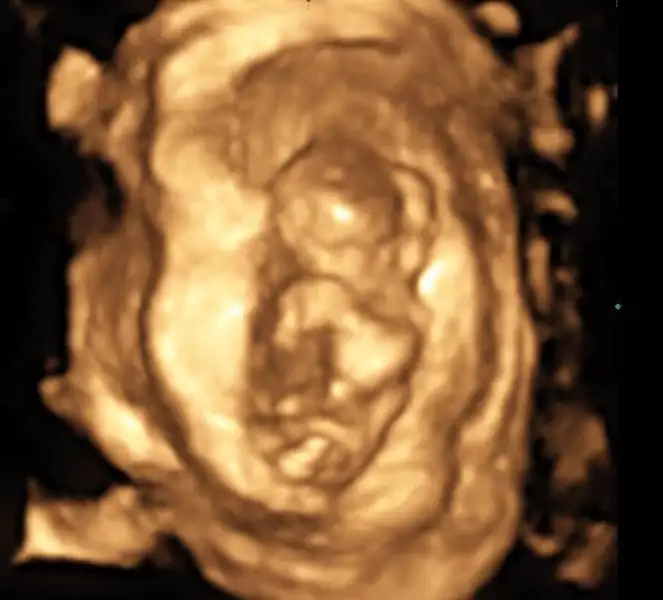

Merhaba, ultrason görüntülerinde sat'a göre 11+4 üz.

cinsiyet tahmini yapabilecek olan var mı:)

IMG_4481.webp IMG_4475.webp IMG_4476.webp IMG_4483.webp